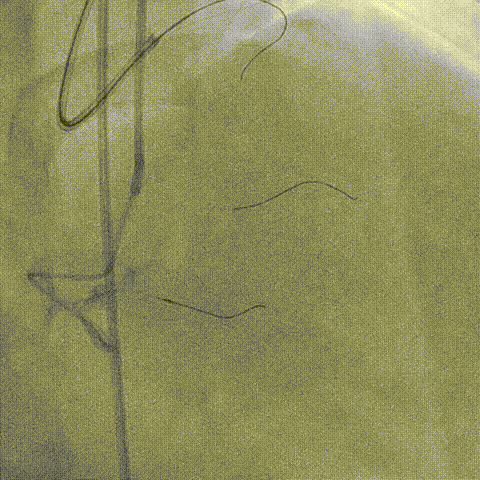

RCA AL 0.75,RCA近段 Ballon Dilatation

RCA Stent Synergy 3.5*20mm

RCA中段重度迂曲、逆向联合Expressman与Mamba,因血管迂曲 Sion无法操控,换用Suoh 03通过间隔支进入LAD